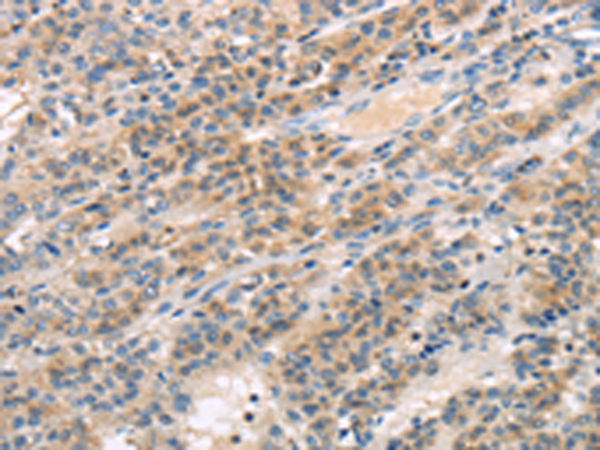

分类: 科研抗体货号: P08926别名: MUTED-TXNDC5应用: WB,IHC反应种属: Human, Mouse